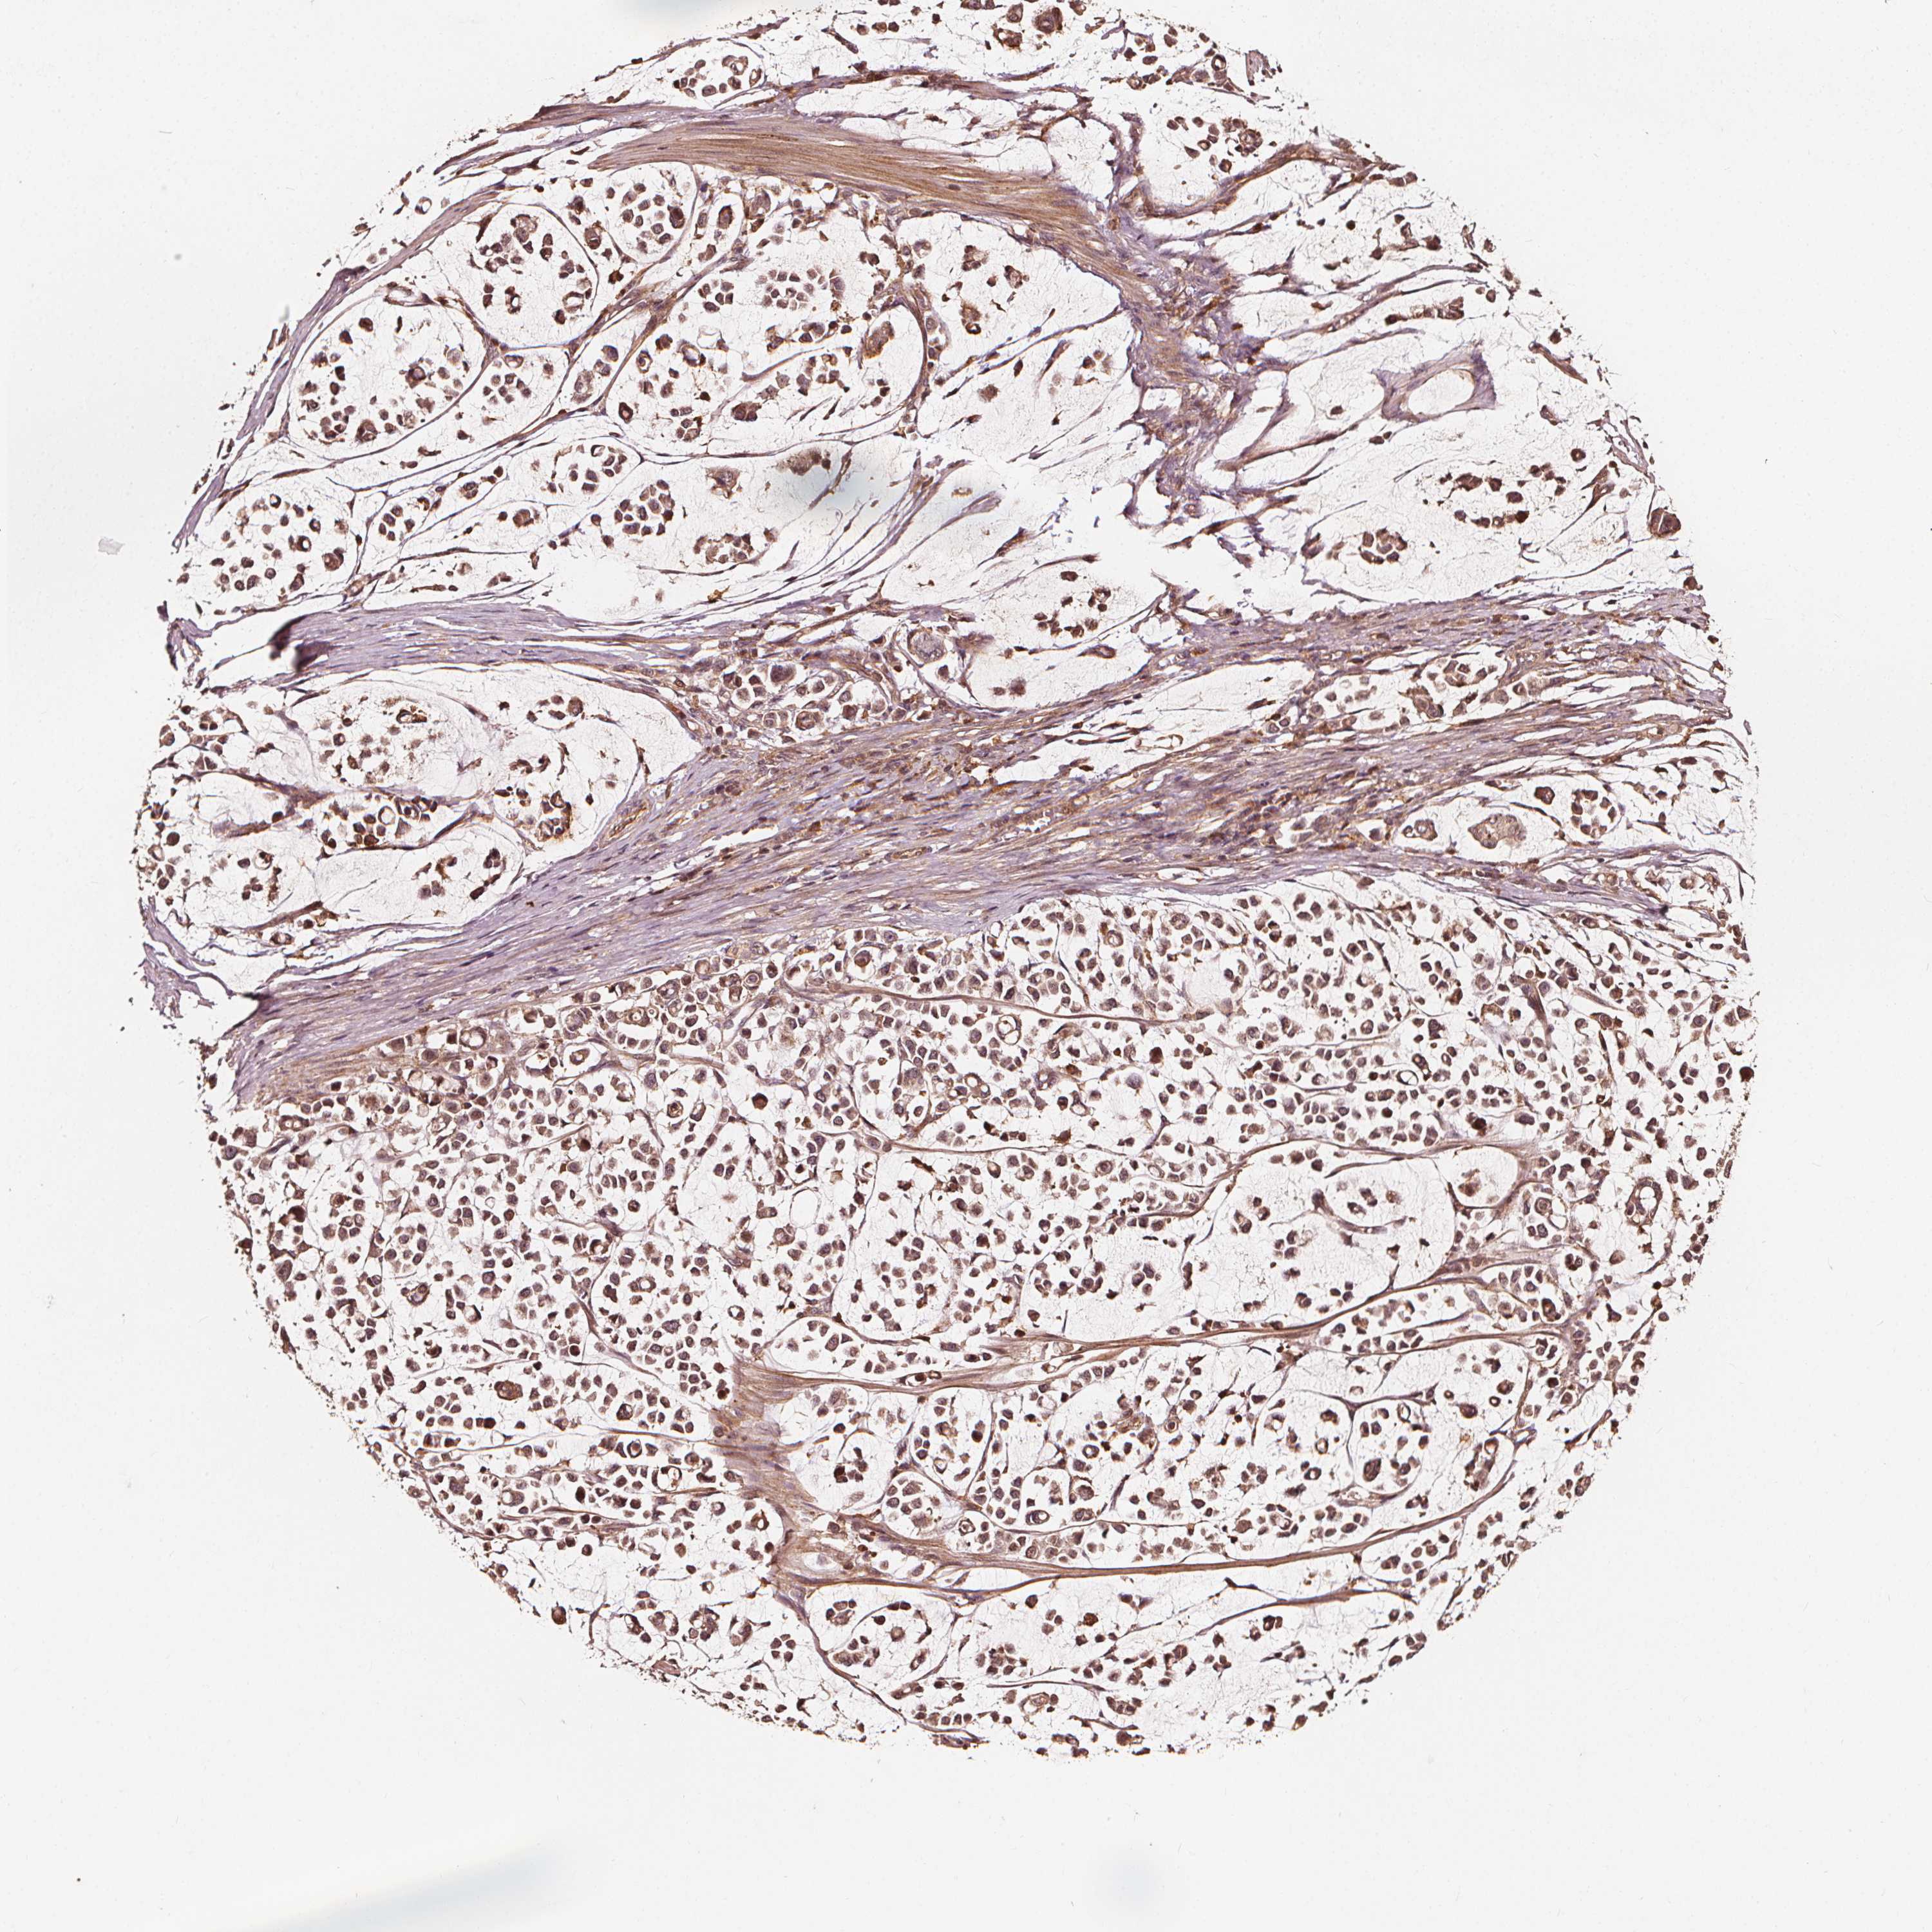

STOMACH CANCER - Protein expressioni

A mouse-over function shows sample information and annotation data. Click on an image to view it in a full screen mode. Samples can be filtered based on level of antibody staining by selecting one or several of the following categories: high, medium, low and not detected. The assay and annotation is described here.

Note that samples used for immunohistochemistry by the Human Protein Atlas do not correspond to samples in the TCGA dataset.

Antibody stainingi

Antibody staining in the annotated cell types in the current human tissue is reported as not detected, low, medium, or high, based on conventional immunohistochemistry profiling in selected tissues. This score is based on the combination of the staining intensity and fraction of stained cells.

Each image is clickable and will lead to virtual microscopy that enables deeper exploration of all samples and also displays staining intensity scores, fraction scores and subcellular localization as well as patient and tissue information for each sample.

Antibody HPA026618

Antibody CAB070132

Staining

High

Medium

Low

Not detected

Intensity

Strong

Moderate

Weak

Negative

Quantity

>75%

75%-25%

<25%

None

Location

Nuclear

Cytoplasmic/membranous

Cytoplasmic/membranous,nuclear

Adenocarcinoma, NOS